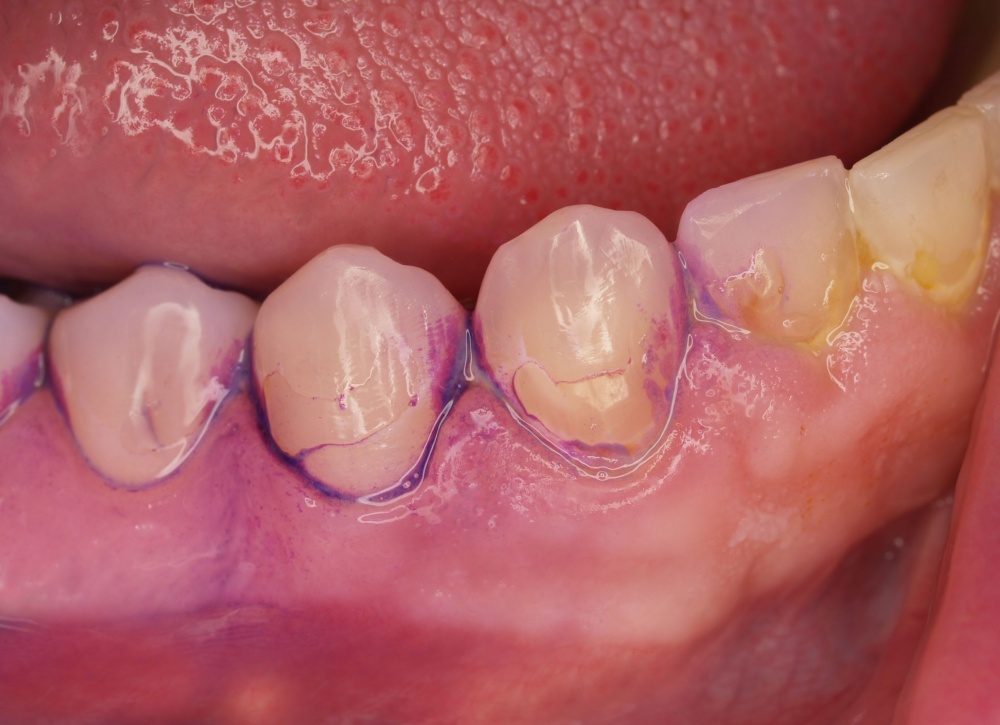

•IP1 – Mundhygienestatus: Darunter versteht man die Beurteilung der Mundhygiene mittels Anfärben der bakteriellen Beläge und der Benutzung eines geeigneten Index, z. B. des Approximalraumplaqueindex (Abb. 6). Für die Beurteilung des Gingivazustandes ist ebenfalls ein geeigneter Index anzuwenden, z. B. der Sulkusblutungsindex.

Im Regelfall werden die individualprophylaktischen Maßnahmen im Rahmen einer einsatzvorbereitenden Prophylaxesitzung durchgeführt. Die Besonderheiten des Einsatzes können Auswirkungen auf das individuelle Mundhygieneverhalten der Soldaten/innen haben, sodass die Durchführung der beschriebenen Maßnahmen im zeitlichen Zusammenhang zum bevorstehenden Einsatz sinnvoll ist. In Abhängigkeit von den jeweiligen klinischen Befunden kann die Entfernung harter und weicher Beläge in dieser Sitzung indiziert sein (Abb. 7). Die Entscheidung darüber trifft jeweils der SanOffz/Zahnarzt.